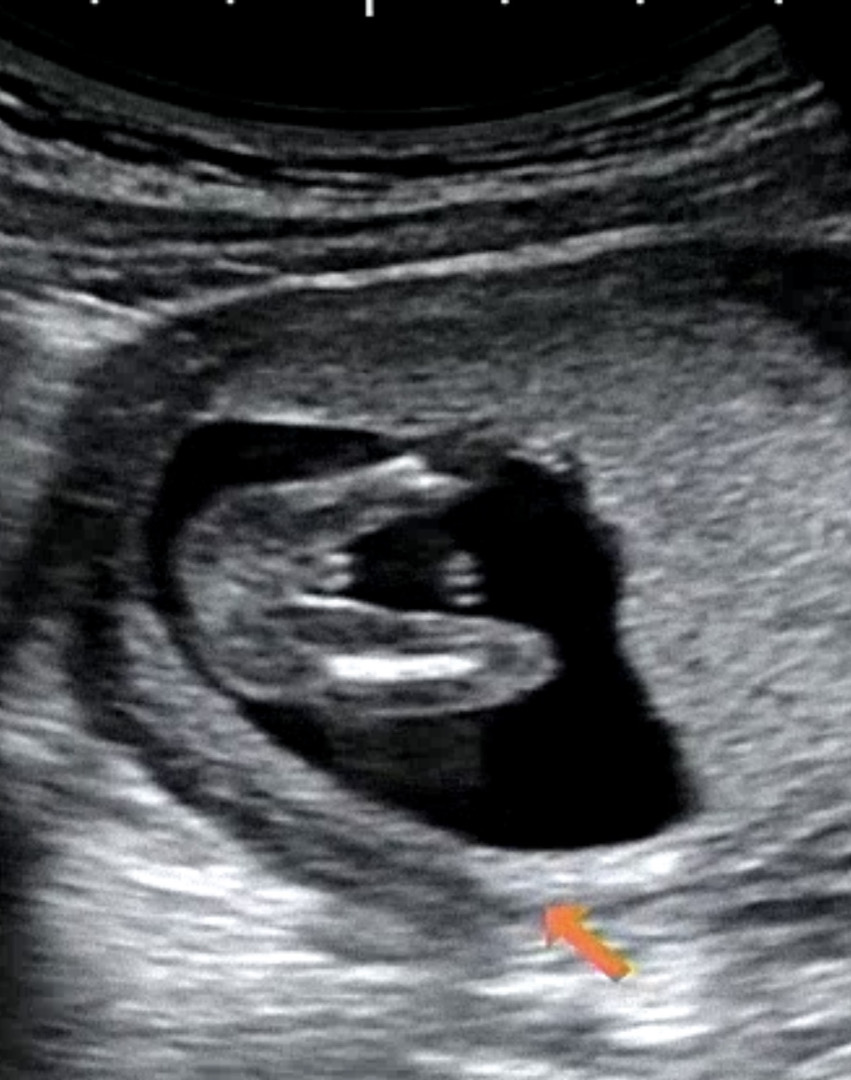

누가 봐도 아덜....

13주차 진료 보러 갔는데 ㅋㅋㅋㅋㅋㅋㅋ 누가 봐도 아들 아니냐며!!!!!! 선생님도 다리 사이에 뭔가 보이긴 하는데.... 하시면서 한참 보다가 꽈츄가 맞는거같은데... 하시네요 아들->딸 반전은 별로 없다믄서요?...

저도 누가봐도 아들이에여 ㅋㅋㅋㅋ 12주차

네 ㅎㅎㅎ 무시할수없는 존재감...

저정도면 존재감 넘 확실한데용 ㅎㅎ